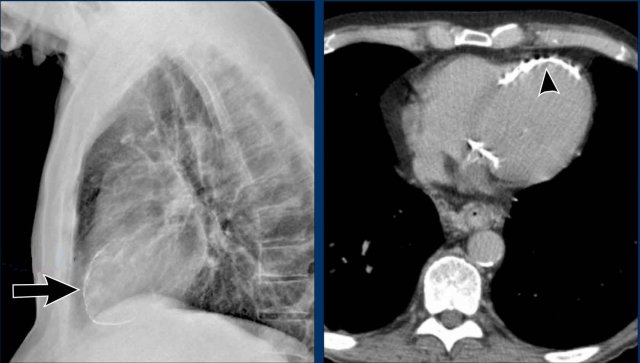

Left Atrial Enlargement

• Patient with a history of chronic mitral valve disease and valve replacement.

• Extreme dilation of the LA leads to bulging of both the right upper cardiac contour (black arrows) and posterior heart border on lateral view (blue arrow).